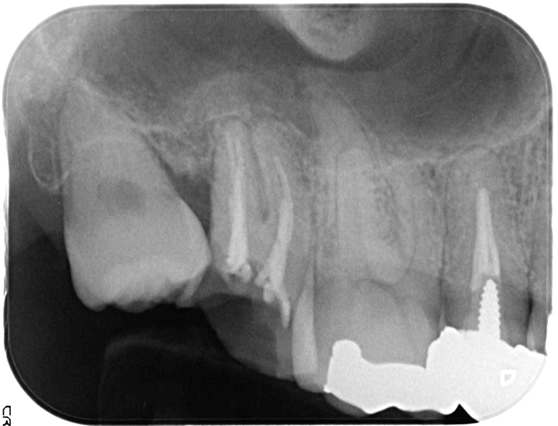

根管治療 症例3

親知らずが影響しているため、根管治療と親知らずの抜歯を提案。

経過観察2年、抜歯後に補綴を行い良好な経過を確認